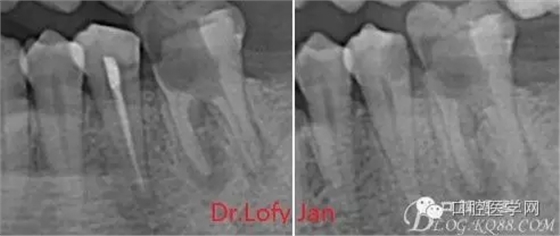

②有助于確定牙根和根管的數(shù)目、位置、形態(tài)、方向和彎曲情況;

⑤評價根管充填的質(zhì)量以及療效。

病例分析:曲面斷層片在x線輔助診斷與檢查中目前大多數(shù)文獻和著作都建議只能作為初診拍片檢查手段,不能作為終末疾病的確診與手術(shù)療效的評價指標,臨床大部分中小型門診都因為設備不齊全導致信息偏差很大。